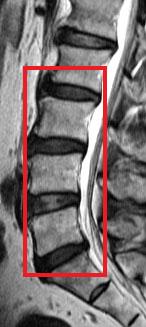

The current study was a cross-sectional assessment of adults from this cohort who were 21 years of age and older. A total of 2,599 individuals were assessed with magnetic resonance imaging (MRI). Amongst them, 27% (n=709) did not have disc degeneration while 73% (n=1,890) had. Of the subjects who have disc degeneration, 7% were underweight, 48% were in the normal weight range, 36% were overweight, and 9% were obese. Overweight and obese individuals were also found to have a greater extent and severity of disc degeneration in comparison to those individuals of normal weight or underweight.